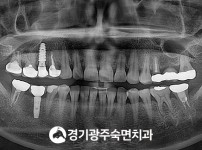

숙면임플란트 3개 - 스트라우만임플란트 (이*웅님)